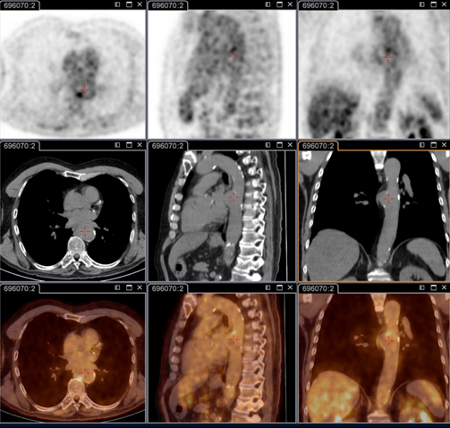

Q fever endocarditis diagnosed at PET scan: 18F-fluorodeoxyglucose PET/CT. In this asymptomatic patient with heart valve history with elevated serology, the PET scan diagnosed an aortic endocarditis on native valve with thoracic and lumbar aortic mycotic aneurysms

Institut Hospitalo-Universitaire Méditerranée Infection (patient consent obtained)

Q fever aortic mycotic lumbar aneurysm diagnosed at PET scan: 18F-fluorodeoxyglucose PET/CT. In this asymptomatic patient with heart valve history with elevated serology, the PET scan diagnosed an aortic endocarditis on native valve with thoracic and lumbar aortic mycotic aneurysms

Q fever aortic mycotic thoracic aneurysm diagnosed at PET scan: 18F-fluorodeoxyglucose PET/CT. In this asymptomatic patient with heart valve history with elevated serology, the PET scan diagnosed an aortic endocarditis on native valve with thoracic and lumbar aortic mycotic aneurysms